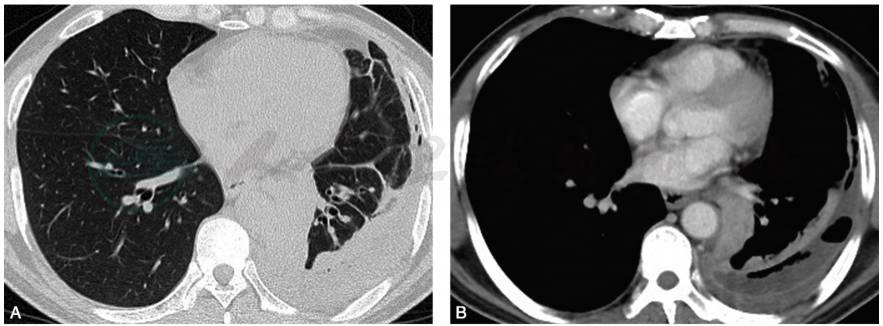

胸部CT(2016-12-4):左侧胸膜腔积液伴左肺不张,右肺胸膜下结节影(图1)。

图1 胸部CT扫描:肺窗提示左肺高密度影,纵隔右移(A、B);纵隔窗提示左侧大量胸腔积液,左肺压缩性肺不张,纵隔明显右移(C、D)